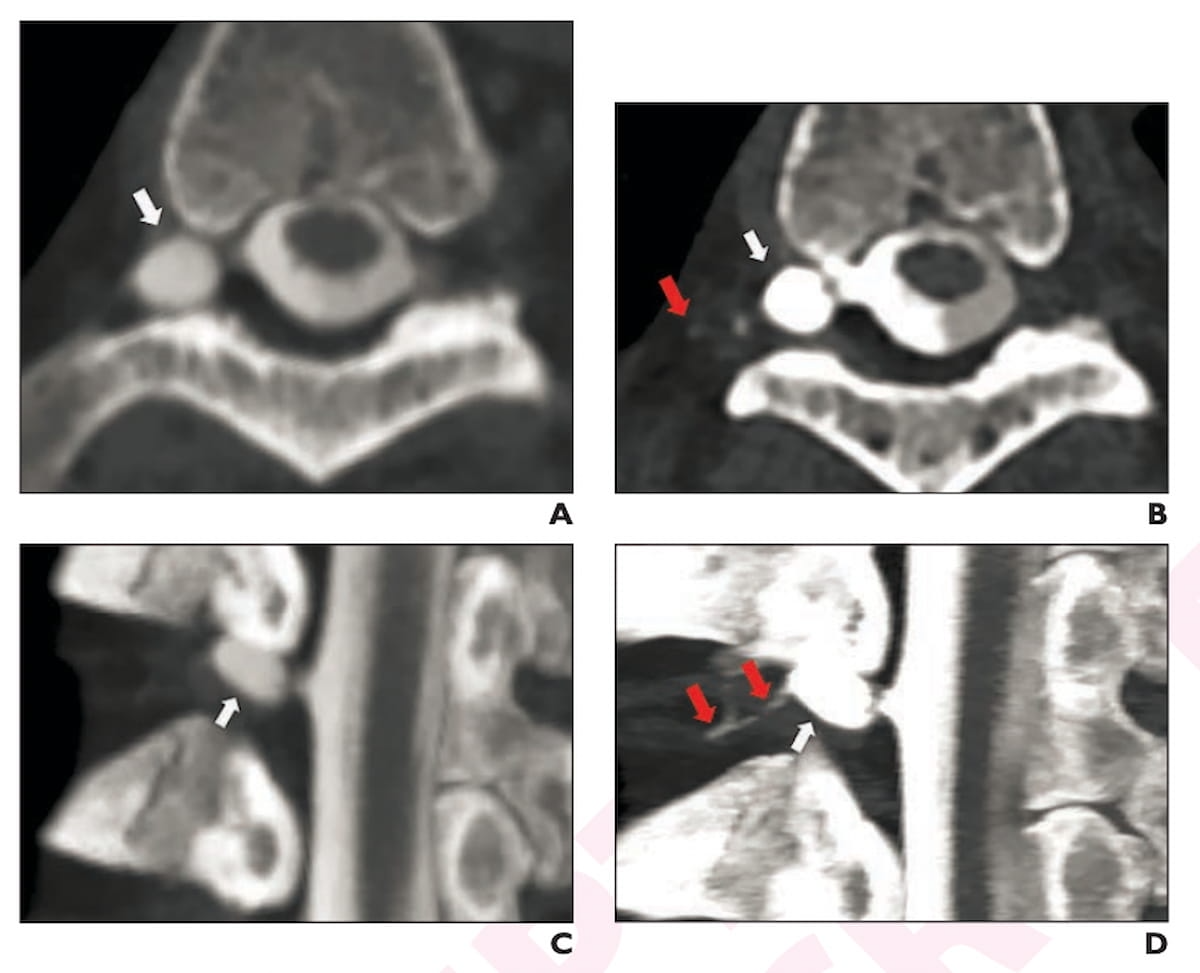

Here one can see energy-integrating detector CT (EID-CT) myelography images (A and B) and photon-counting detector CT (PCD-CT) myelography (C and D) for a 57-year-old man with two years of symptoms for spontaneous intracranial hypotension (SIH). The PCD-CT images were obtained a year and a half after the EID-CT images. None of the three reviewing radiologists detected cerebrospinal fluid-venous fistula (CVF) with the EID-CT images but all three radiologists diagnosed the CVF on PCD-CT images. (Images courtesy of the American Journal of Roentgenology.)